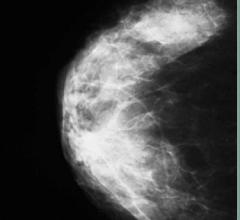

The women’s health channel includes news, videos, podcasts and other content related to technology used to detect and treat breast cancer and cervical cancer, including mammography, breast magnetic resonance imaging (MRI), automated breast ultrasound (ABUS), breast ultrasound, breast biopsy and breast radiation therapy.

Despite decades of progress in breast imaging, one challenge continues to test even the most skilled radiologists ...

The last 20 years have brought about great advances in breast cancer detection and treatment. Among them has been the ...